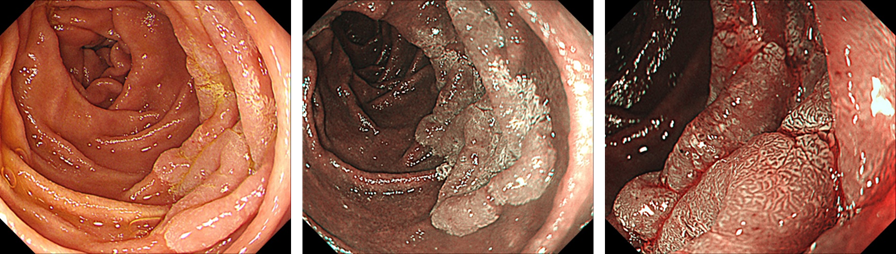

结合病变特征(局限于黏膜层、无淋巴结转移),符合内镜下治疗指征,但该病变大,行全院多学科讨论后,该手术于手术室完成,必要时胃肠外科介入,充分与患者及家属沟通,患者及家属表示知情同意,遂对十二指肠降段早期癌行ESD手术治疗。术中完整剥离病灶送检,创面见小穿孔,因创面较大,多次尝试奥林巴斯尼龙绳结扎装置结合安杰思夹子装置行荷包缝合失败,术中请胃肠外科进一步行创面外科手术缝合,外科手术缝合顺利。

image.png

图3 十二指肠降段早期癌ESD剥离后创面和标本

ESD标本术后病理:第2-18条组织高级别异型增生,局部(黏膜内癌,中分化),镜下肿瘤范围约:41.4 mm×21.0 mm,肉眼类型:0-IIa ,水平切缘(0),垂直切缘(0)。

3月后患者无明显症状,复查胃镜可见十二指肠降段见吻合口及吻合钉,吻合口黏膜未见异常,肠腔无明显狭窄。

图4 十二指肠降段早期癌术后3个月创面愈合情况